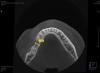

denis1987 Опубликовано 7 августа, 2013 Поделиться Опубликовано 7 августа, 2013 Вот такой вот пациент, планируется имплантация в области 46 зуба , снимки прилагаются. Вопрос в следующем, как лучше расположить имплант относительно антагониста, потому что не могу на КТ при позиционировании нормально попасть в плоскость с ним... Имплант планирую ставить 4.2 х 10, так как до НЧ канала 12.3 мм. Ссылка на комментарий